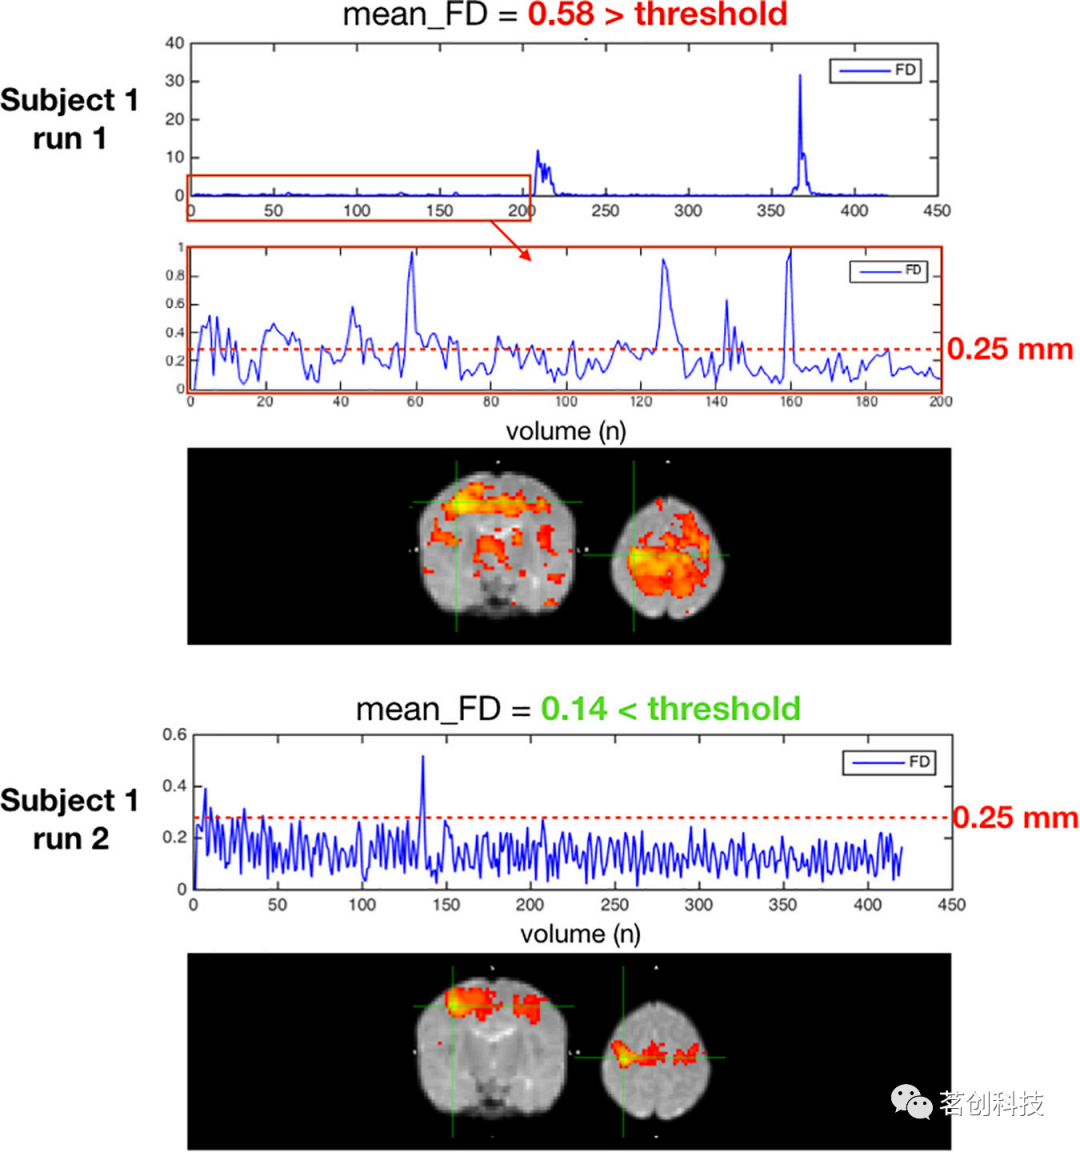

高运动被试

高运动采集是伪影的来源,可能会混淆与非神经信号的神经相关性。除了基于FD的单帧运动检测外,NeoRS还评估每次BOLD run的平均FD。默认情况下,NeoRS设置为丢弃平均FD高于0.25mm的采集序列。可以通过定义options.FDaverage在配置文件中更改平均FD阈值。

图10是一个具有2种(运动量)不同rsfMRI采集的单被试示意图,在基于种子点的运动网络功能连接结果中,平均逐帧位移高于0.25 mm(run 1)的采集与平均逐帧位移低于0.25 mm(run2)的采集之间的差异。从图中可以看到,高运动采集会导致噪声增加,并且脑网络拓扑难以识别。

图10.一个高运动被试的两次采集示意图。